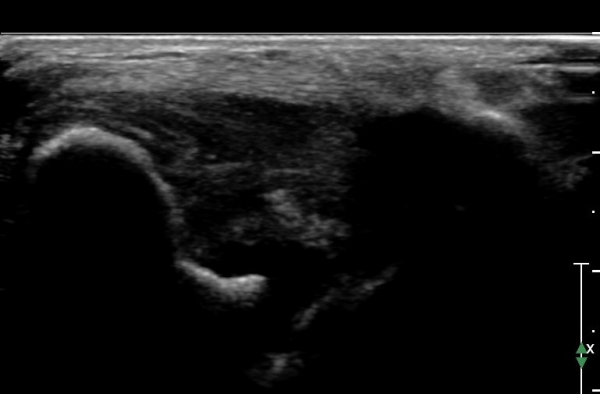

ÃÊÀ½ÆÄ °Ë»ç :  ¹ß¸ñ ¾ÕÂÊ Á¾´Ü¸é°Ë»ç¿¡¼­ ƯÀÌ ¼Ò°ß º¸ÀÌÁö ¾Ê´Â´Ù(»çÁø 1)